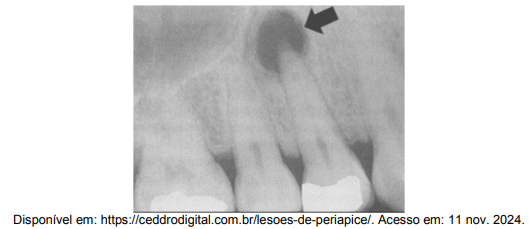

A imagem a seguir mostra uma radiografia de um dente com uma lesão periapical visível na região do ápice.

Considerando essa condição clínica, qual o resultado mais esperado em um teste de vitalidade realizado com Endo Ice?